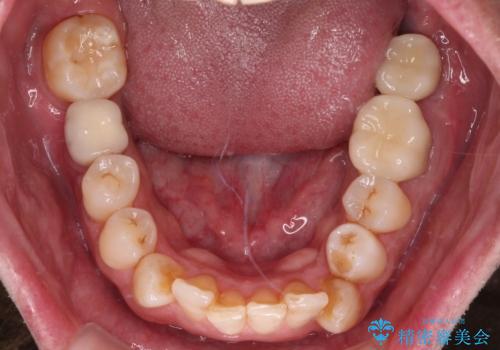

- 近医にて奥歯の抜歯が必要と言われたとのことで来院された患者様です。

診査の結果、歯が破折しており、抜歯が必要な状態でした。

最後方歯であるため、入れ歯かインプラントかどちらかの補綴治療を行うこととなりますが、ご希望によりインプラント補綴治療を行うこととしました。